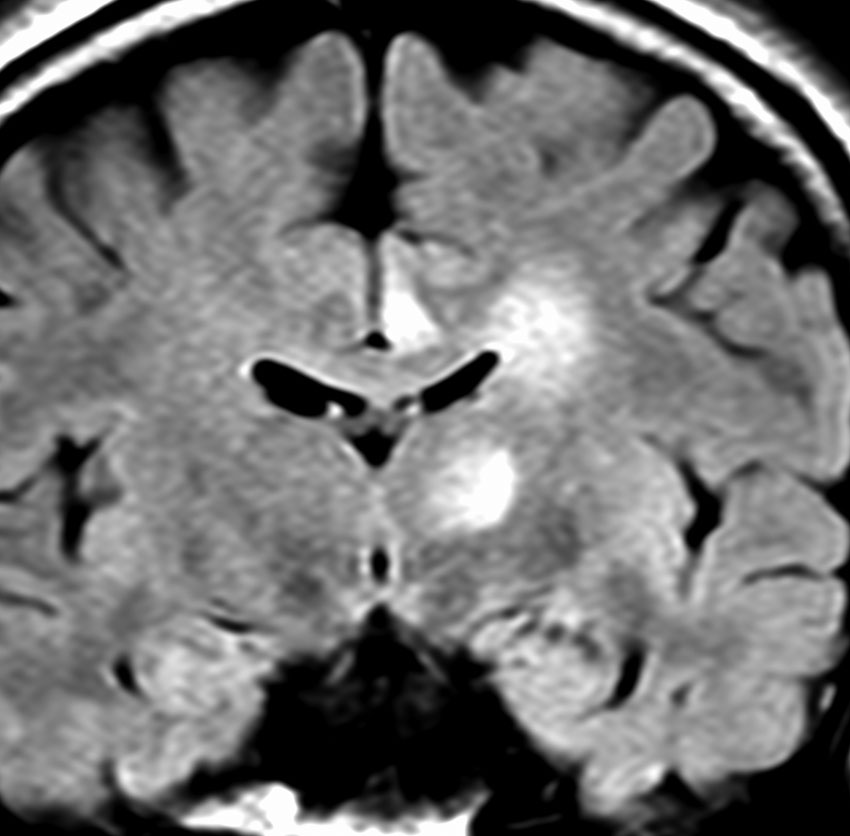

グリオマトーシス gliomatosisのような例

病理組織診断で退形成性星細胞腫 WHO grade IIIとされるものに,全く違った性質を示すグリオーマがあります。

ゆっくり進行する軽い右麻痺で発症した50歳くらいの患者さんです。脳梗塞や脱髄疾患を疑われていました。左頭頂部皮質下から脳梁,内包,中脳大脳脚まで非常に広範囲に浸潤しています。single cell infiltrationという浸潤形態を想像させます。右下はT!ガドリニウム造影で,この部分だけが増強所見があります。

おそらく今後は,diffuse hemispheric glioma WHO grade 4と診断されます。

軽度の異型性を認め,細胞密度が高く核分裂が目立ち,Ki-67 (MIB)染色率は20%に達しました。1p/19q欠失はなくMGMTメチレーションもありませんでした。IDH変異は調べていない年代の例で不明です。病理組織診断でanaplastic astrocytomaとされました。治療は,全脳に近い照射野となるので50Gy/25分割が限界でした。TMZを併用しています。

照射後も症状は一度も改善することなく悪化して,数ヶ月後にはもともと腫瘍が見えなかった内側側頭葉に大きな腫瘍塊が発生増大しました。この例は退形成性星細胞腫と診断するしかなかったものですが,2020年時点でははっきり分類できない星細胞系腫瘍です。